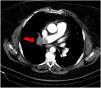

This is the case of a 61-year-old woman with obesity, hypertension, and chronic obstructive pulmonary disease (COPD) who presented to the emergency room with clinical signs of dyspnea and pleuritic pain in right hemothorax of 10-day evolution. She showed significant respiratory effort, which is why non-invasive mechanical ventilation (NIMV) was started. Thoracic X-ray looked normal, and the electrocardiogram performed revealed the presence of a dilated—though normocontractile—right ventricle. The thoracic ultrasound revealed the presence of a triangular hypoechogenic image of peripheral base that was consistent with right pulmonary infarction (Fig. 1). The axial thoracic computed tomography (CT) scan showed a repletion defect in the right pulmonary artery spreading towards the lobar branches plus pulmonary alveolar damage to the right upper lobe suggestive of associated pulmonary infarction (Fig. 2). The ultrasound provides extremely valuable additional information—essential at times—for the optimal management of the patients. The most indicative finding on the thoracic ultrasound of pulmonary thromboembolism (PTE) is the presence of triangular hypoechoic lesions and pleural base surrounded by a pleural line of normal aspect with or without associated pleural effusion.